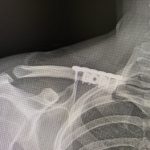

Plastic Surgery Case Study – Reductive Shoulder Reshaping Combined With Rib Removal Waistline Narrowing Surgery

Background: Shoulder narrowing surgery is done in either transgender male to females or cis-females for shoulder dysphoria. Having done many such procedures at this point I have had the epiphany that the term ‘shoulder narrowing’ does not accurately describe what occurs. Because the clavicle is a lazy s-shaped bone with a horizontal orientation, a removal Read More…